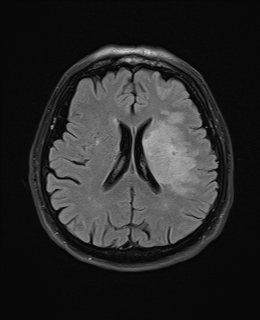

| T2 FLAIR | T2 |

|---|---|

![]() |

| T2-Weighted (T2WI) | CSF, edema, demyelination, most pathology | Fat, calcification, acute haemorrhage | Pathology detection (tumours, inflammation, MS plaques) |